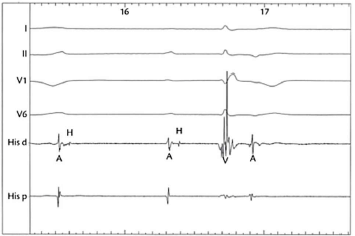

Um senhor de 68 anos com BRE prévio foi submetido a um EEF devido à síncope. Durante o posicionamento de um cateter no ventrículo direito, houve assistolia de 4s, com retorno a ritmo próprio, como mostrado na figura a seguir.

Figura 1:

O cateter quadripolar foi retraído para a região do feixe de His, revelando o traçado mostrado na segunda figura.

Figura 2:

Assinale a opção que indica o que foi observado.